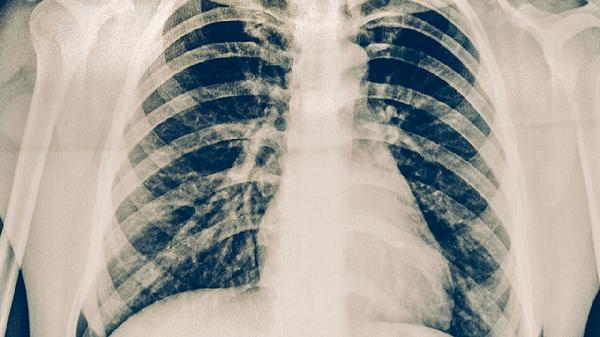

肺炎可通过抗感染治疗、对症支持治疗、氧疗、免疫调节、并发症管理等方式控制,常用药物包括阿莫西林克拉维酸钾片、盐酸左氧氟沙星胶囊、布洛芬混悬液、氨溴索口服溶液、醋酸泼尼松片等。肺炎通常由细菌、病毒、真菌等病原体感染引起,建议及时就医,在医生指导下规范用药。

肺炎患者应保持室内空气流通,每日开窗通风2-3次。饮食选择高蛋白易消化食物如蒸蛋羹、鱼肉粥,避免辛辣刺激。恢复期可进行呼吸训练如缩唇呼吸,逐步增加活动量。戒烟并避免二手烟暴露,寒冷季节注意保暖。遵医嘱完成全程治疗,定期复查胸片评估疗效。